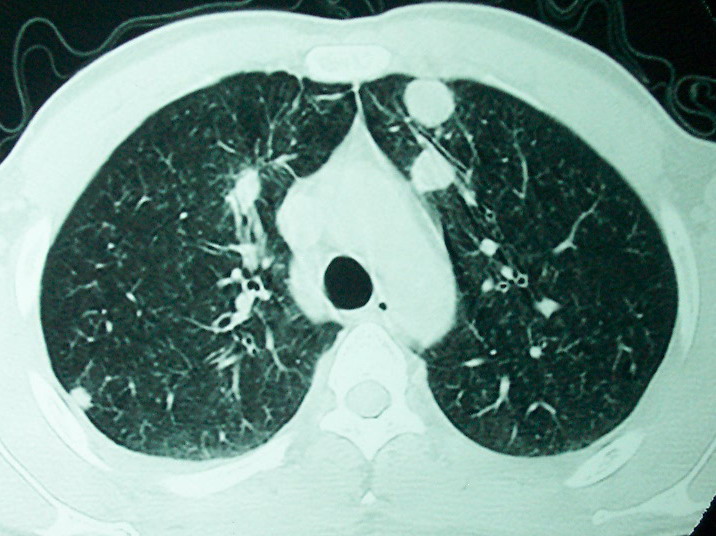

血源性肺脓肿,一般由原发感染灶引起脓毒败血症,在肺部形成小脓肿,病变变化快,容易形成肺气囊,脓气胸,主要与转移瘤鉴别,通过临床病史可分

结合临床发热,咳痰考虑为血源性肺脓肿,不过双肺结节又在肺的边缘,还是小心一点,抗炎后复查吧

除了肺内多发结节和左肺下叶的浓疡病灶,还应注意满肺散在的小结节影,还有右上肺前段支气管内膜不光整这些细节,结合病史,肺内多发结节应考虑结核性肉芽!